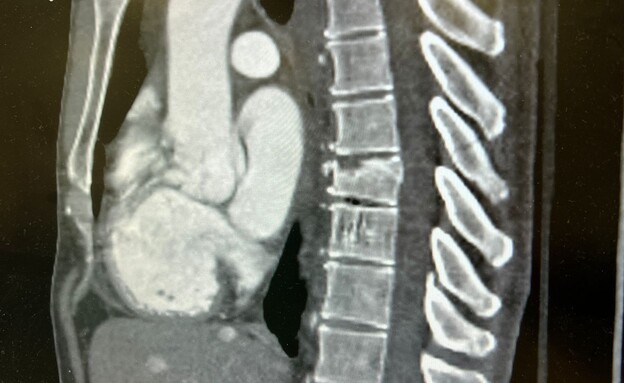

לאחר כמה רגעים, עובר אורח שהיה עד לאירוע הזעיק עזרה והעניק לו סיוע ראשוני עד להגעת צוותי מד"א. הוא פונה לבית החולים במצב קשה לחדר הלם, כשהוא סובל משבר בחוליות בגב ודימום משמעותי בפניו. בשעות אלה הוא מאושפז בבית החולים. אשתו סיפרה ל-N12 כי "זה מקרה מצער ולא נתפס". לדבריה, "איך אפשר להאמין שספורטאי מצליח סופג התעללות כל כך קשה וכל חטאו שרכב על אופניו במסלול הקבוע שהוא רגיל אליו".